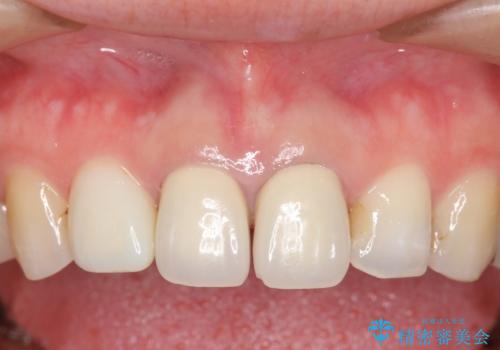

- 上顎の前から2番目の歯の古い樹脂をセラミックにしたいといらっしゃった方の症例です。

古い樹脂を除去後、オールセラミッククラウンによる補綴を行いました。

- オールセラミッククラウン…¥100,000×2、仮歯…¥10,000×2費用は治療当時の料金となります

今回用いたオールセラミッククラウンはジルコニアフレームという白い素材の上にセラミックを盛っているため、審美性が非常に高いのが特徴です。

また、ジルコニアは人工ダイヤモンドの材料にも使われているほど高い強度を持っており、そのためオールセラミッククラウンは審美性だけでなく、奥歯やブリッジの補綴も可能とするクラウンです。